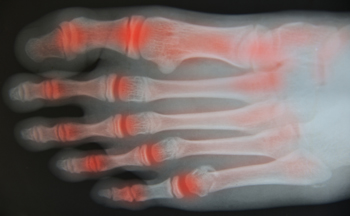

Arthritis can affect the joints in the feet, leading to pain, stiffness, and swelling. The most common type is osteoarthritis, which occurs due to the gradual wear and tear of joint cartilage, often caused by injury, overuse, or genetics. Rheumatoid arthritis, or RA, is an autoimmune disease that leads to inflammation and damage in the joints, including those in the feet. Psoriatic arthritis, another autoimmune disorder, can cause swelling in the toes and changes in the nails, such as pitting. Additionally, gout is a type of arthritis that results from the accumulation of uric acid in the joints. Gout often affects the big toe and causes intense pain and swelling, especially at night. Common symptoms of arthritis in the feet include difficulty walking, tenderness, and visible changes in the joints or nails. If you are experiencing foot pain that may be caused by arthritis, it is suggested that you schedule an appointment with a podiatrist for a diagnosis and appropriate treatment options.

Arthritis is a joint disorder that involves the inflammation of different joints in your body, such as those in your feet. Arthritis is often caused by a degenerative joint disease and causes mild to severe pain in all affected areas. In addition to this, swelling and stiffness in the affected joints can also be a common symptom of arthritis.